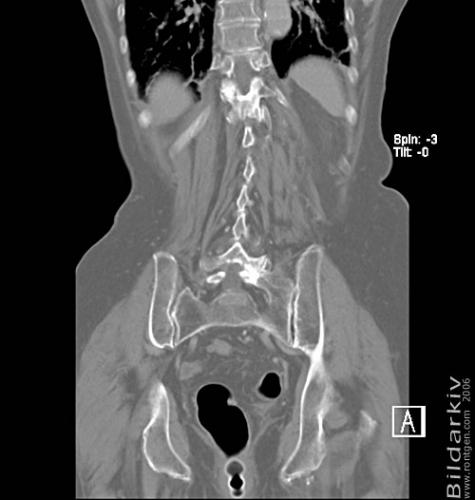

CT colon 40

Datortomografi av tjocktarmen (colon) med infunderad luft i tarmen samt med kontrast i blodbanan. Koronar bildserie.

CT multislice 16